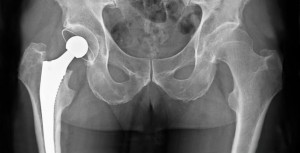

Reemplazo total de cadera o entrenamiento de resistencia para la osteoartritis grave de cadera

En un ensayo clínico que comparó el reemplazo total de cadera con el entrenamiento de resistencia en pacientes con osteoartritis de cadera grave y con indicación de cirugía, el reemplazo de cadera condujo a una mayor reducción del dolor y una mejor función a los 6 meses. New England Journal of Medicine, 30 de octubre de 2024.

¿Cuánto tiempo dura un reemplazo de cadera? ¿Y el de rodilla?

De acuerdo a lo observado en grandes registros nacionales, puede esperarse que el 58% de los reemplazos de cadera y el 82% de los de rodilla duren 25 años.The Lancet, 16 de febrero de 2019